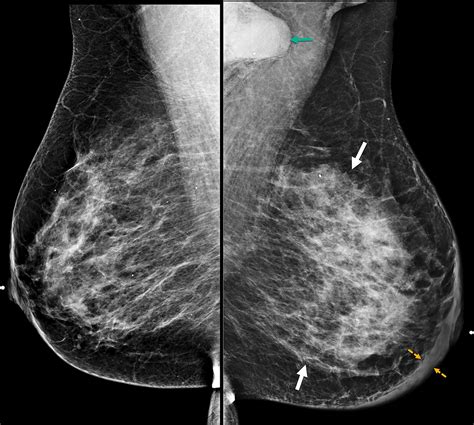

Now, let’s talk about mammography , the tried-and-true workhorse of breast imaging. While mammograms might not always show a distinct tumor in IBC, they are still a crucial part of the initial workup. Why? Because they can reveal diffuse skin thickening and increased breast density , which are hallmarks of IBC. Radiologists meticulously examine the mammograms for these subtle, yet significant, signs. They’ll be looking for the characteristic “peau d’orange” appearance, which means the skin looks thickened and pitted, much like the skin of an orange. They also assess for increased vascularity and trabecular thickening. Even if a specific mass isn’t visible, these findings, combined with the clinical symptoms, raise a strong suspicion for IBC, prompting further investigation with other imaging modalities. It’s like looking for clues in a puzzle; sometimes the picture isn’t clear from one piece alone, but when you put several subtle clues together, the overall image becomes much more evident. For mammography to be most effective in cases of suspected IBC, specialized views might be employed, and sometimes a comparison with previous mammograms is invaluable to track any changes over time. Remember, guys, mammograms are still a cornerstone, but they are often just the beginning of the radiological investigation when IBC is suspected. The radiologist’s trained eye is essential here, differentiating between benign inflammatory changes and the malignant processes characteristic of IBC. It’s a delicate dance of interpretation, ensuring no stone is left unturned in the quest for an accurate diagnosis.